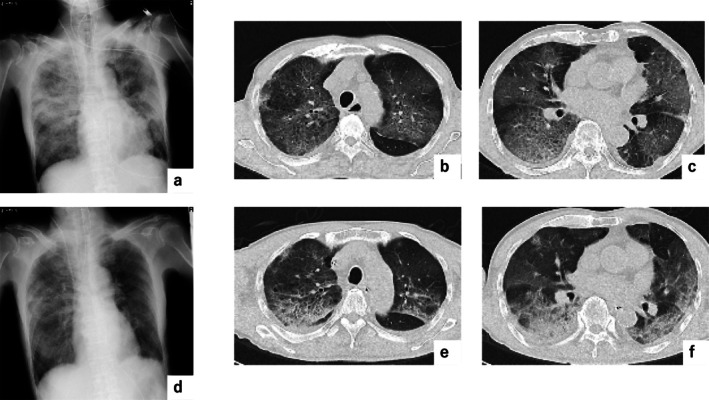

Coronavirus disease 2019 (COVID-19) has resulted in global morbidity, mortality, and societal disruption. COVID-19 mRNA vaccination was mandatory in many countries for a period; however, severe adverse events have been observed in some individuals who received the vaccine. We report a case of COVID-19 mRNA vaccine-induced pneumonitis in a male patient whose cytokine levels were analysed prior to admission. His serum IgE level was high (347 U/mL), and several cytokines were elevated: TNFα was 1.2 pg/mL, IL-6 was 156 pg/mL, and IL-8 was 75.0 pg/mL. The patient developed severe respiratory failure requiring ventilatory support but recovered after steroid pulse therapy.